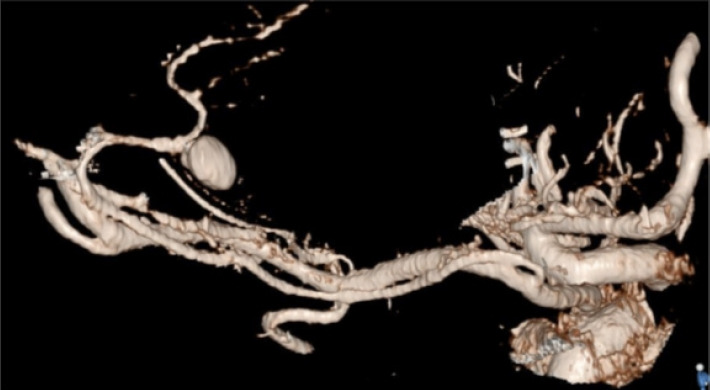

Aneurysms of the pineal region are rare and theoretically could arise from the medial posterior choroidal artery (MPChoA) or lateral posterior choroidal arteries (LPChoA). A 64-year-old lady with subarachnoid haemorrhage (SAH) and intraventricular haemorrhage (IVH) due to a ruptured MPChoA aneurysm was treated with microsurgical aneurysm excision via an occipital interhemispheric approach. This case demonstrates the importance of being mindful of rare aneurysm locations when initial vascular imaging in SAH appears normal.

松果体区域的动脉瘤是罕见的,理论上可能起源于内侧后脉络膜动脉(MPChoA)或外侧后脉络膜动脉(LPChoA)。一位64岁的女性因MPChoA动脉瘤破裂而出现蛛网膜下腔出血(SAH)和脑室内出血(IVH),经枕半球间入路行显微手术切除动脉瘤。本病例表明,当SAH的初始血管成像显示正常时,注意罕见动脉瘤位置的重要性。